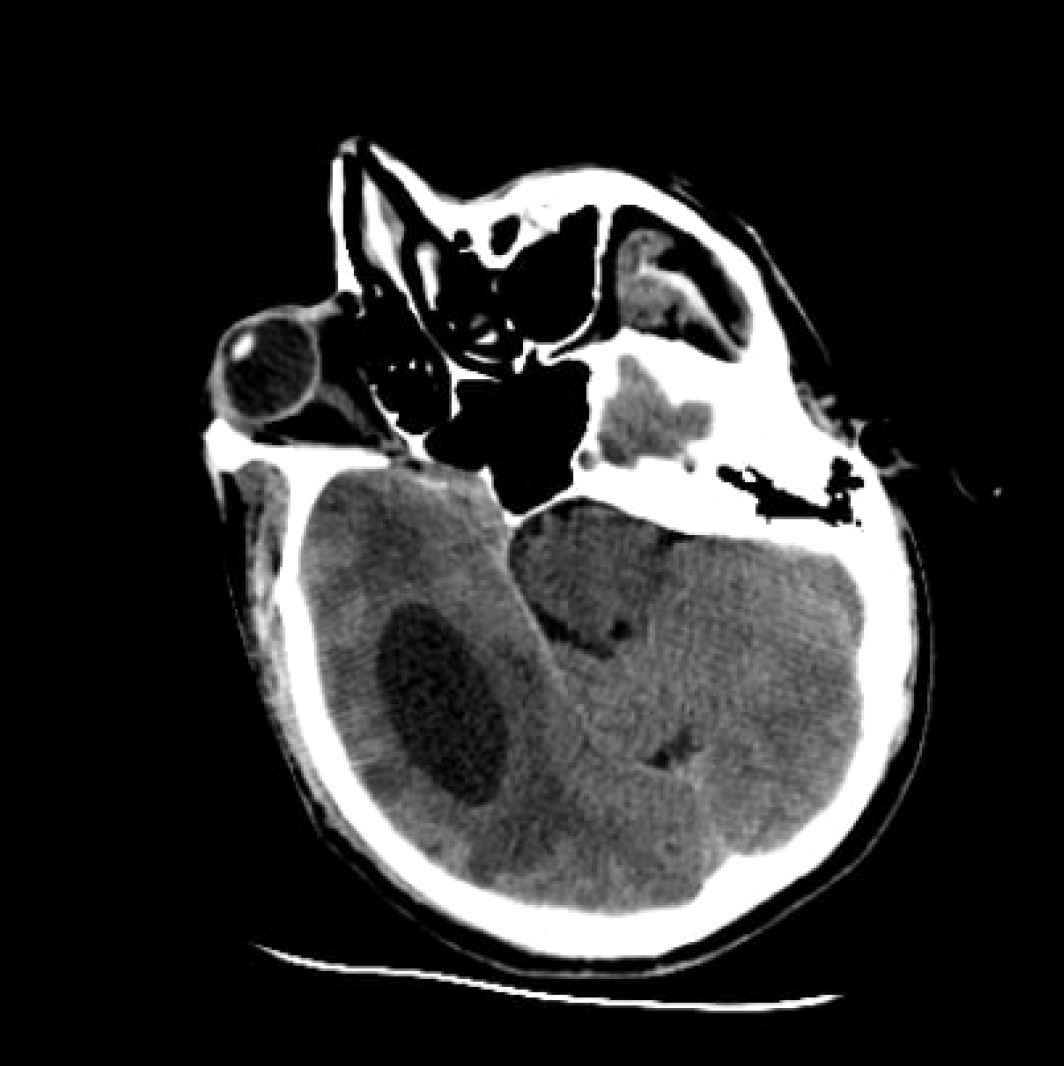

Şekil 1. Beyin Bilgisayarlı Tomografisinde Sağ Paryetotemporal

Bölgede Çevresel Ödem Eşliğinde Hipodens Kistik Lezyon.

Beyin bilgisayarlı tomografisi (BT)’nde sağ parietotemporal bölgede 4.5 × 4 cm boyutlarında, çevresinde ödem bulunan kistik lezyon izlendi ve görünüm öncelikle malignite lehine yorumlandı (Şekil 1). Kontrastlı beyin manyetik rezonans görüntüleme (MRG)’de, sağ temporal lobda T1 sekansında hipointens, FLAIR’da hiperintens, internal membranöz yapılar içeren, kalın kapsüllü, çevresinde vazojenik ödem bulunan, periferal kontrast tutan 63 × 33 mm boyutunda kitle lezyonu saptandı. Sağ lateral ventrikül kompresyonu ve orta hatta sola doğru kayma mevcuttu (Şekil 2).